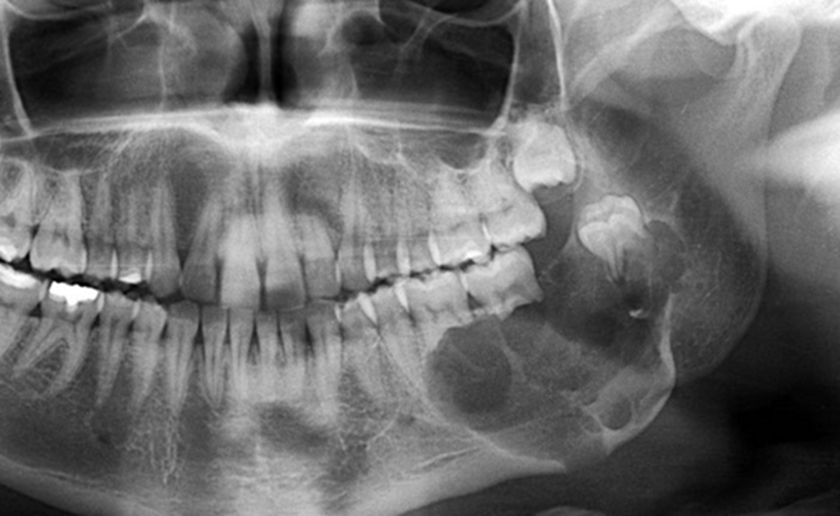

Hình X-quang chẩn đoán ung thư xương hàm

U xương hàm là tình trạng xuất hiện khối u phát triển bất thường trong xương hàm trên hoặc hàm dưới, có thể là u lành tính hoặc ác tính. Bệnh không phổ biến như sâu răng hay viêm nha chu nhưng lại âm thầm và dễ bị bỏ qua vì triệu chứng ban đầu khá mờ nhạt. Nguyên nhân gây u xương hàm rất đa dạng. Một số trường hợp liên quan đến rối loạn phát triển mô răng, u nguyên bào men, u xương lành tính. Trường hợp ác tính có thể là ung thư xương nguyên phát hoặc ung thư từ cơ quan khác di căn đến xương hàm. Ngoài ra, tiền sử viêm nhiễm răng miệng kéo dài, chấn thương vùng hàm mặt, tiếp xúc tia xạ, yếu tố di truyền hoặc đột biến gen cũng được xem là yếu tố nguy cơ.

Tác động của u xương hàm lên sức khỏe không chỉ dừng ở vấn đề thẩm mỹ. Khi khối u phát triển, người bệnh có thể thấy sưng nề vùng má hoặc lợi, đau âm ỉ, tê môi cằm, răng lung lay không rõ nguyên nhân, khó nhai hoặc há miệng hạn chế. Nếu là u ác tính, khối u có xu hướng xâm lấn nhanh, phá hủy cấu trúc xương, lan vào xoang hàm, hốc mắt hoặc nền sọ. Điều này có thể gây biến dạng khuôn mặt, suy giảm chức năng ăn nhai, nói chuyện và ảnh hưởng nghiêm trọng đến tâm lý người bệnh.